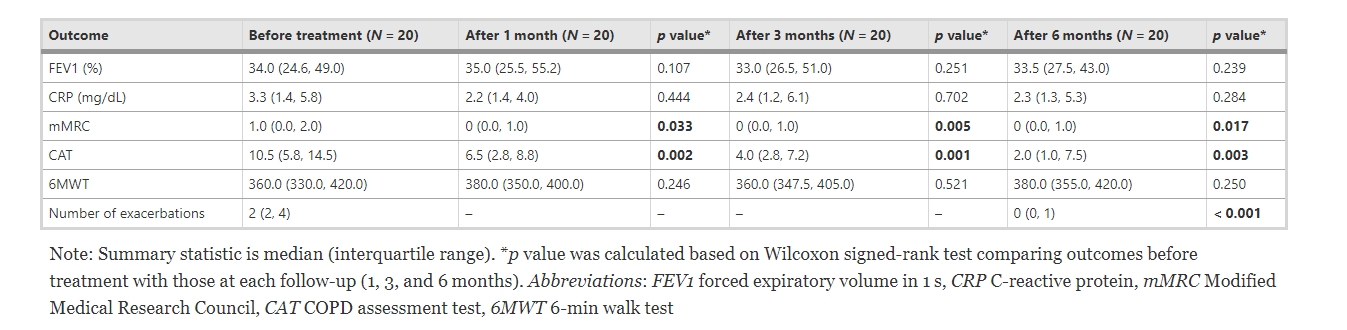

有效性評(píng)估

1.根據(jù)GOLD分期進(jìn)行治療前和隨訪期間的臨床結(jié)果評(píng)估

- 治療前(34%) 和治療后1(35%)、3 (33.0%) 和6(33.5%) 個(gè)月的FEV1均略有改變 (p>0.05)。

- 平均CRP水平從治療前的3.3mg/dL分別下降到治療后1、3和6個(gè)月的2.2、2.4和2.3 (mg/dL)。

- 6MWT從治療前的360.0分別增加到治療后1、3 和 6 個(gè)月的380、360.0和380.0 (p>0.05)。

- 與治療前相比,治療后1、3 和6個(gè)月的mMRC、CAT評(píng)分和發(fā)作次數(shù)均顯著下降,且這種下降趨勢(shì)在治療后1~6個(gè)月內(nèi)持續(xù)。

- 治療后1、3和6個(gè)月,mMRC值從治療前的1.0顯著下降為0.0(p<0.05)。

- 同樣,CAT評(píng)分也從治療前的10.05顯著下降為治療后1個(gè)月的6.5、治療后3個(gè)月的4.0和治療后6個(gè)月的2.0(p<0.05)。COPD發(fā)作次數(shù)從治療前的2次顯著減少為治療后6個(gè)月的0(p<0.05)。